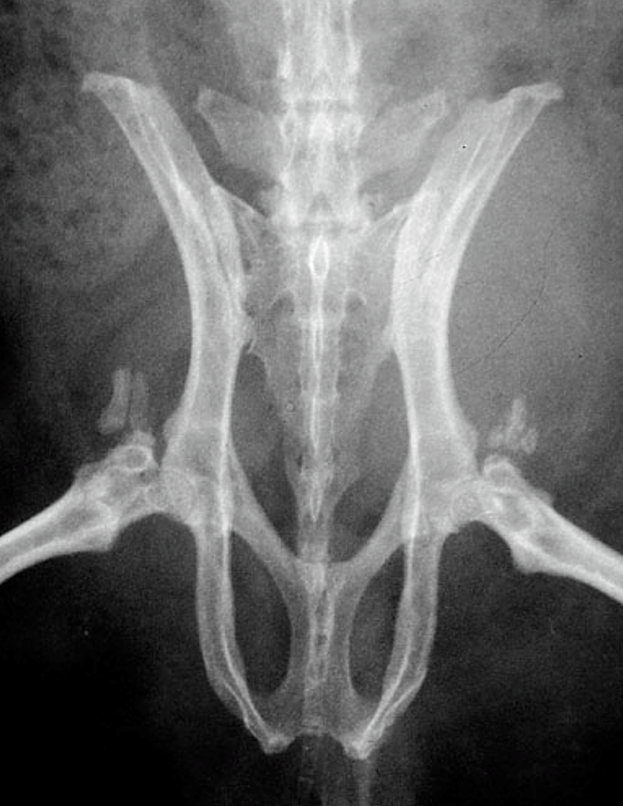

線維性骨異栄養症

骨が線維化を起こして脆くなる病態で、骨折を起こしやすくなります。通常の外傷による骨折とは発生の意味合いが異なります。線維性骨異栄養症を引き起こす原因として、副甲状腺機能亢進症(上皮小体機能亢進症)があげられ、過剰に副甲状腺ホルモン(PTH:parathormone:パラソルモン)が分泌された結果、骨に影響を与えます。モルモットの副甲状腺の裏側で甲状腺葉に囲まれて位置しています〔Zabel et al.1986〕。副甲状腺機能亢進症には副甲状腺自身の異常を原因とする原発性副甲状腺機能亢進症とカルシウム代謝の破綻を原因とする二次性副甲状腺機能亢進症とに区別され、モルモットでは後者の二次性副甲状腺機能亢進症が主です。副甲状腺ホルモンの過剰な分泌は、血中のカルシウム濃度が低下すると分泌が高まり、骨に含まれているカルシウムを血中に溶出させ、腎臓に作用してリンの再吸収を抑制し、カルシウムの再吸収を促して尿中への排泄を減らします。 また、腎臓におけるビタミンDの活性化を促進して、活性型ビタミンDの作用によって腸管からのカルシウムの吸収を増加させます。骨のカルシウムを血液中に溶出させることから、骨が線維化を起こして、骨痛や骨変形・病的骨折などの原因となります〔Hawkins et al.2012〕。また、過剰な副甲状腺ホルモンは、身体の様々な場所へのカルシウムを沈着(異所性石灰化)させたり、心臓血管系、胃腸腸管、胆嚢、気管、子宮および精管の平滑筋の弛緩も引き起こすと言われています〔Motomura et al.1998,Kline et al.2000〕。二次性副甲状腺機能亢進症は幼体に好発する栄養性副甲状腺機能亢進症と中高齢に好発する腎性副甲状腺機能亢進症があげられます。栄養性副甲状腺機能亢進症はカルシウムとリンの摂取量が不均衡、ビタミンDの不足が原因です。しかし、モルモットにおける明確な文献などの報告は少なく、これまでの報告では10ヵ月齢のメス、2歳のオス、1歳のオスのモルモットで発生した例があるに過ぎません〔Rapsch et al. 2009,Schwarz et al.2001〕。腎性副甲状腺機能亢進症は慢性腎不全になりやすい中高齢にみられ、腎臓でのリンの排泄およびビタミンD3の活性化ができなくなります。また活性化ビタミンD3が低下すると、腸管からのカルシウムの吸収が低下します。